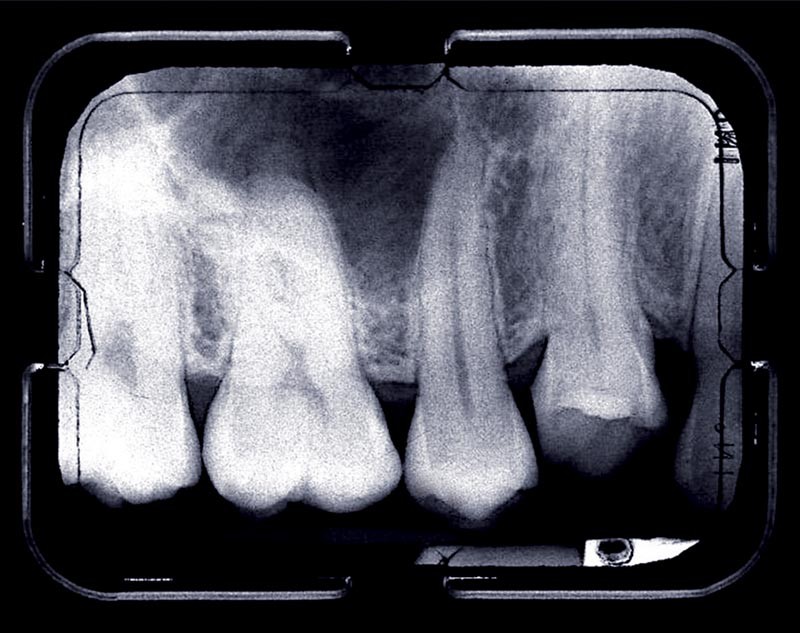

L’orthodontie pourra ensuite avoir lieu normalement, sous réserve qu’il n’y ait pas de dents ankylosées ; les examens cliniques (son métallique à la percussion, infraclusion) et radiologiques (absence de ligament alvéolo-dentaire) nous auront permis de poser le bon diagnostic. Des forces légères devront être appliquées, en particulier si des mouvements radiculaires sont envisagés (ingression, torque). En effet, les traumatismes dentaires potentialisent les risques de résorptions radiculaires post-orthodontiques [2, 3].